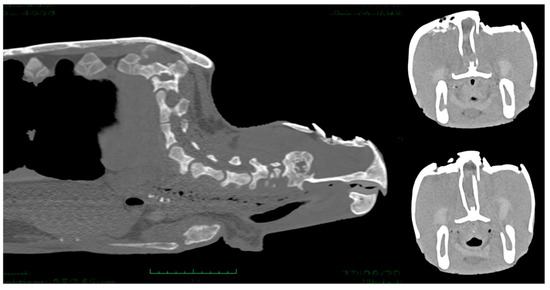

A neurologic examination was performed to evaluate neurological deficits. General activity, neck, front and rear flipper movements, and pupillary, eyelid, menace responses and cloaca reflexes were observed. Mentation was assessed and classified in three degrees: 1. alert (responsive to external stimuli); 2. depressed (reduced, but appropriate responsiveness to external stimuli); 3. lethargic/comatose (not responsive, loss of consciousness) [12]. Loggerhead sea turtles underwent a total body radiograph in dorso-ventral (DV), latero-lateral (LL) for each side, and craniocaudal (CrCd) radiographic examinations plus dorso-ventral (DV) and latero-lateral (LL) of the skull. In cases of moderate/severe head injuries and all cases of neurological symptoms or involvement of the sense organs, a multi-detector computed tomography (MDCT) with a 16-slice MDCT scanner (Somaton Emotion, Siemens, Forchheim, Germany) was performed. The technical scan and reconstruction parameters were 110 KVp, 180 mAs, 1 mm slice thickness, pitch of 0.8, 0.6 s/rotation, 0.5 mm reconstruction interval, and standard (bone) acquisition algorithm. Three-dimensional (3D) multi-planar reformatted, maximum-intensity projection and volume-rendered images were obtained using a dedicated 3D software program (Pixmeo OsiriX DICOM viewer®, Pixmeo, Bernex, Switzerland) (Figure 2).

Total head and body examinations by CT scan were performed on 20 turtles. Sea turtles with a neurological score of 3 (n = 6) did not undergo general anesthesia for CT scan examination, those with a neurological score of 1 (n = 14) received general anesthesia, with 5 mg/kg propofol (Propovet®, Zoetis, Rome, Italy) injected intravenously (IV) via the external jugular vein. The images were then submitted to 3D and MPR (OsiriX, Pixmeo Sàrl). In severe cases, evaluation of the CT images revealed the presence of depressed comminuted fractures of the parietal, postorbital, prefrontal, frontal, orbital, nasal, and squamosal bones. All lesions were most lytic with no formation of new bone tissue. In eight turtles, some of the fragments appeared inverted toward the disrupted dura, and pneumocephalus and cerebral lacerations and cerebral swelling were detected (Figure 7).

Figure 7. CT scan images showing comminuted fractures of the parietal, postorbital, prefrontal, and frontal bones. The lesions were lytic and skull fragments appeared inverted toward the disrupted dura, pneumocephalus and cerebral lacerations and cerebral swelling are evident.